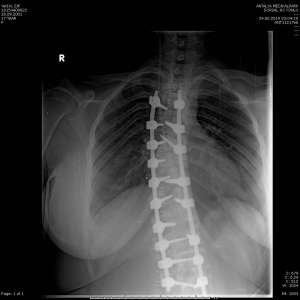

Skolyoz tanısı ayakta çekilen tüm omurgayı içine alan röntgen filmi ve klinik muayenede yukarıda sayılan belirtilerin bir veya birkaçının bulunması ile konulur. Skolyoz tanısı konulduğunda sebebe yönelik MR incelemesi gereklidir.

Ayakta çekilen tüm omurganın ön arka ve yan radyografilerinde, eğriliğin başladığı ve sonlandığı omurlar arasındaki açı ölçülür ve bu açının ilerlemesine göre takip edilir. Bu açıya Cobb açısı denir.

40 derecenin üzerindeki eğriliklerde ve büyüme potansiyelinin devam ettiği hastalarda cerrahi tedavi tek seçenektir. Cerrahi tedavi sırt ve bele yerleştirilen implantlar (vida-çubuk) yardımıyla başarılı bir şekilde yapılabilmektedir.

Skolyoz Görselleri